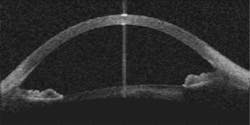

Carl Zeiss Meditec (Jena, Germany) has developed prototype OCT systems for imaging the anterior chamber of the eye in collaboration with Dr. David Huang and colleagues at the Cleveland Clinic (Cleveland, OH). Retinal imaging systems, which are becoming the standard of care in ophthalmology, image at 820 nm to penetrate the water within the eyeball and at powers low enough to be safe for the sensitive retinal tissue, while the anterior chamber imagers use more powerful 1300-nm light sources for rapid imaging of anterior chamber features such as the iris and cornea (see figure)."Probably the biggest potential application that will affect a lot of people is Phakic intraocular lenses (IOLs)," said Matt Everett, senior program manager for optical imaging. In Europe in particular, the placement of IOLs has been gaining favor as an alternative to surgical procedures to reshape the cornea. Simply placing a lens behind the cornea significantly reduces the tissue damage and subsequent healing associated with the procedure. Successful placement of a Phakic IOL requires precise measurement of the anterior chamber, however, which can be obtained through anterior-chamber imaging. Anterior chamber imaging, which also has possible applications in glaucoma and LASIK procedures, Everett said.